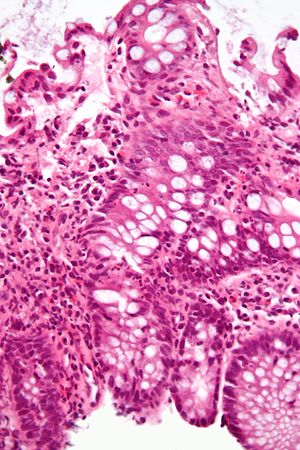

A micrograph demonstrating cryptitis, a microscopic correlate of colitis. H&E stain.

An important investigation in the assessment of colitis is biopsy. A very small piece of tissue (usually about 2mm) is removed from the bowel mucosa during endoscopy and examined under the microscope by a histopathologist. It can provide important information regarding the cause of the disease and the extent of bowel damage.